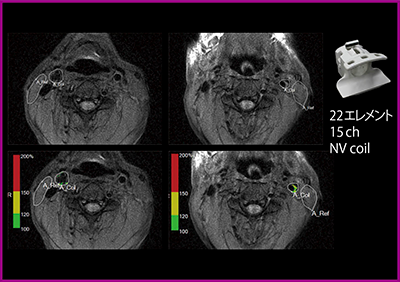

RADARを活用した検査が,プラークイメージングである。プラークの性状を鑑別する画像には,高T1コントラスト,拍動アーチファクトの抑制,血流信号の抑制が必要である。プラークイメージング法について,非同期SE法,同期併用SE法,RADAR-2D SE法を比較した検討1)では,RADAR-2D SE法がT1コントラスト,血管壁描出,血流信号抑制のすべてにおいて良好であったと報告している。

頸動脈プラークイメージング撮像の位置決めではMRAのMIP画像を用いて,総頸動脈から内外頸動脈の分岐部を中心に設定する。ECHELON OVALのコンソール上で,血管と近傍の軟部組織(胸鎖乳突筋など)にROIを囲むと,出血性プラークは赤,脂肪性プラークは黄,線維性プラークは緑に色分けされたカラーマップが表示される(図4)。

図4 RADAR-SE法によるプラークイメージング